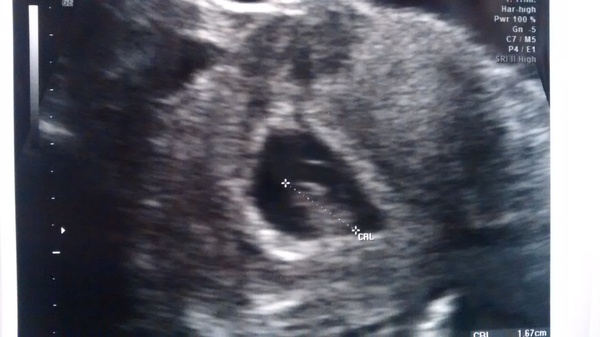

Went for a private scan this afternoon. I'd been trying to resist having one but gave in. All well, one little bean with a heartbeat and measuring about the right size. Have a small fibroid too but not too worried about that. DH and I went for an Indian afterwards. I'm with you all on the tiny portions - the staff kept coming to check it was OK as I'd eaten barely half of it. It was lovely.

Lovely scan pic missis Smile

Thanks tea